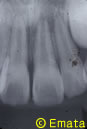

8歳・男の子のケース

夕方5時頃自転車で転倒して、前歯のおとなの歯が完全に抜け出てしまいました。(完全脱臼脱離)

根が完成されていなかったため、神経もとらずにすみました。